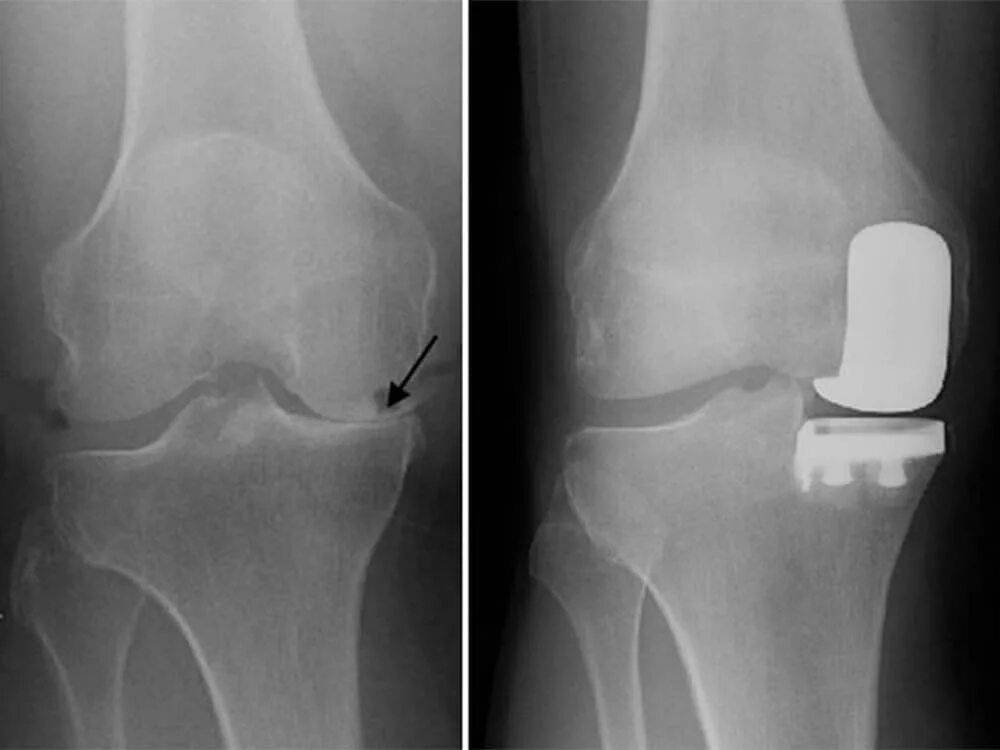

В каком случае меняют сустав